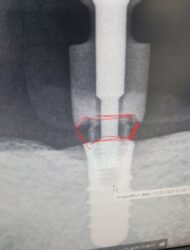

I have a patient with a fractured Straumann tissue-level implant at site #31. The coronal portion of the implant has fractured off circumferentially, leaving only the bone-level portion intact. This implant previously supported a gold crown on a one-piece abutment. Additionally, the tissue-level implant at site #30 has a worn… Read more

I would love to see what the remaining platform looks like. It may surprise us!

If the remaining piece is fractured in a way that an abutment would leave some irregular gaps and holes, you may consider using your impression coping to try to capture the shape of the remaining fractured implant. You can do that by applying light body…